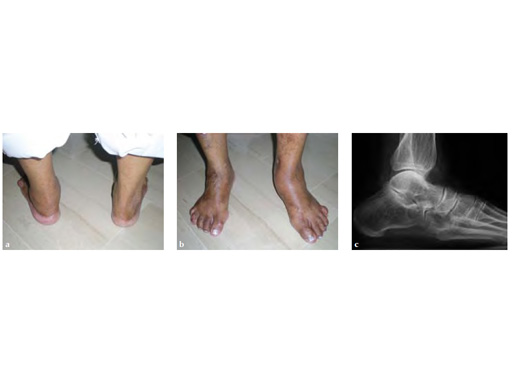

Case 2: 67-year-old white female

Case provided by Juan Bernardo Gerstner Garcs, Cali, Colombia

Stage II of her left posterior tendon dysfunction and tarso/metatarsal, instability visible on x-ray (see Fig 1a-c).